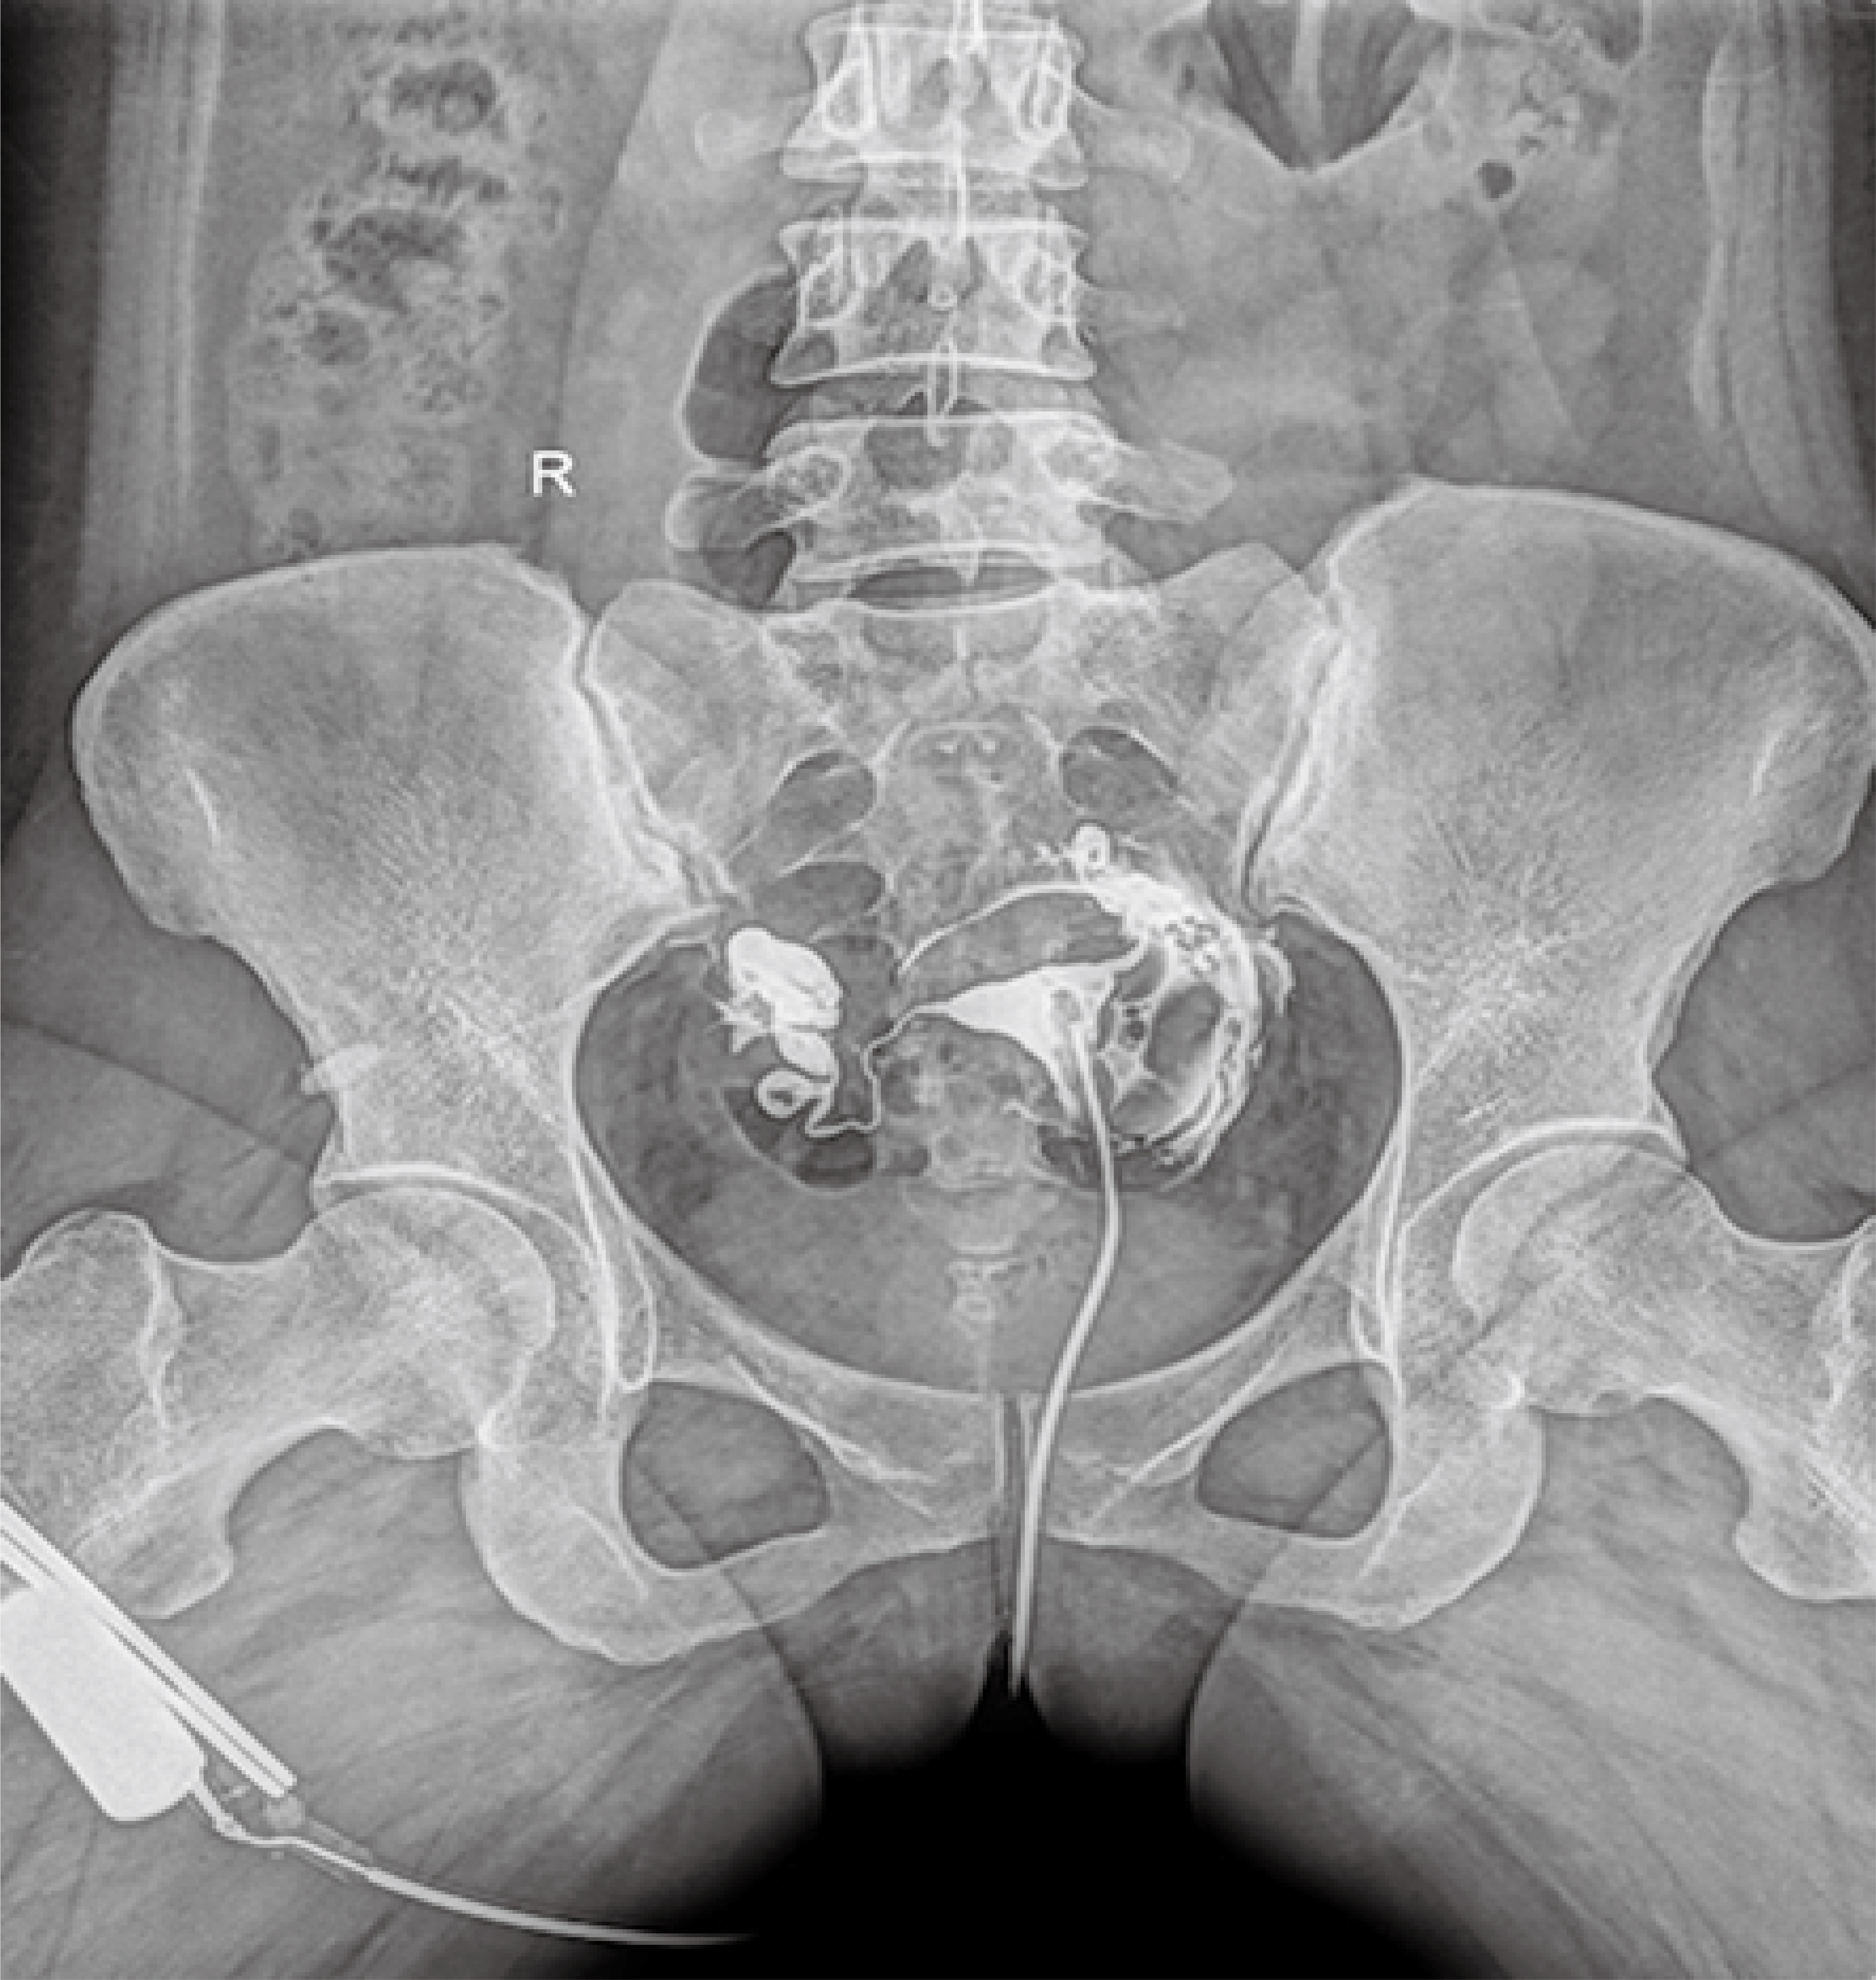

● 在可視過程或回放過程中,如發現疑似病灶,可進行毫秒級高清點片,隨時抓取單幀圖像,精準捕抓病灶。

球管傾斜攝影角度-45°~45°,滿足臨床各部位各角度的攝影需求。如:髕骨軸位、頸椎正位、骶尾椎、鼻竇瓦氏位、梅氏位等部位檢查。

點片裝置移動范圍大,無需患者移動就能完成全身各部位的檢查;